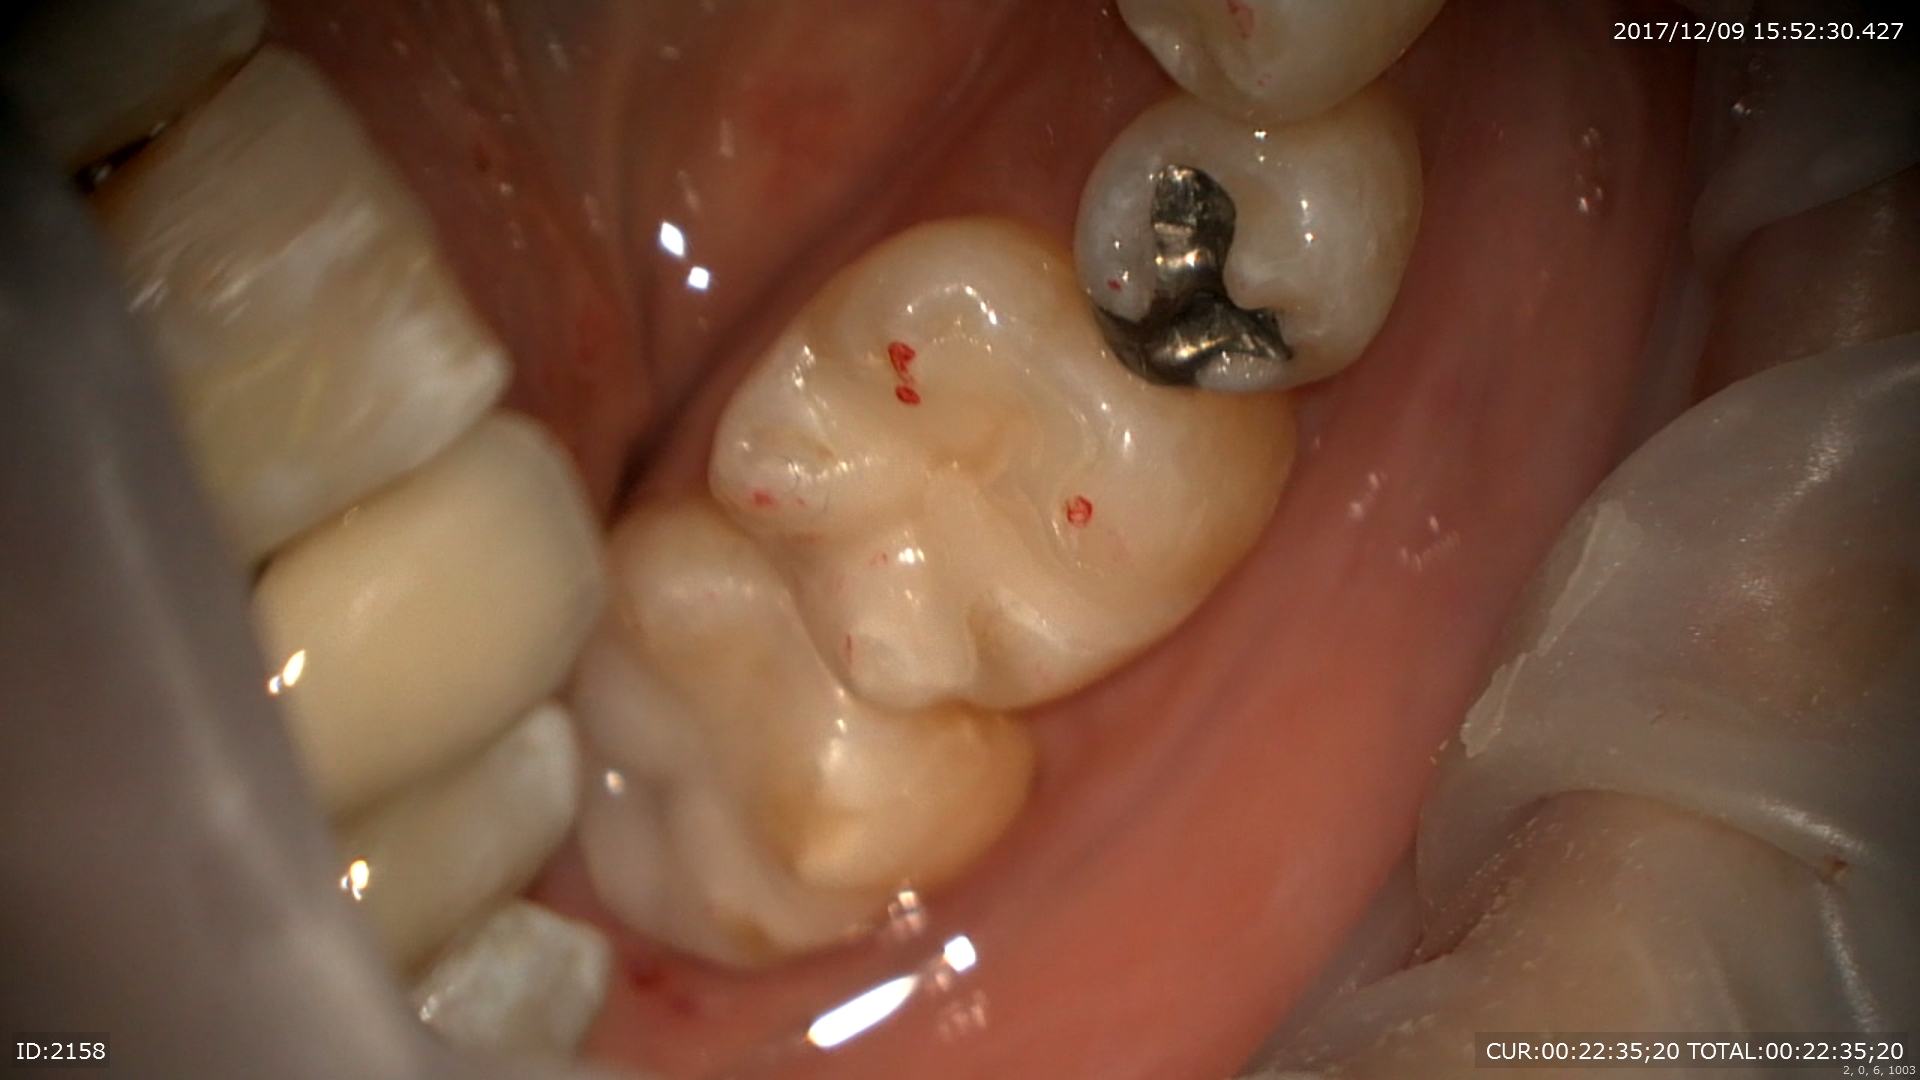

次は虫歯のケース。プラスチックはこのように汚れ(細菌)を寄せ付け二次虫歯を発生させます。

外すと あらま。感染だらけ。マイクロスコープで丁寧に無痛で。

感染を取るとこんなに歯がなくなってしまいます。裸眼でとったら神経見えるかも。。

MTAで神経保護

また神経に優しい治療ができて幸せ!